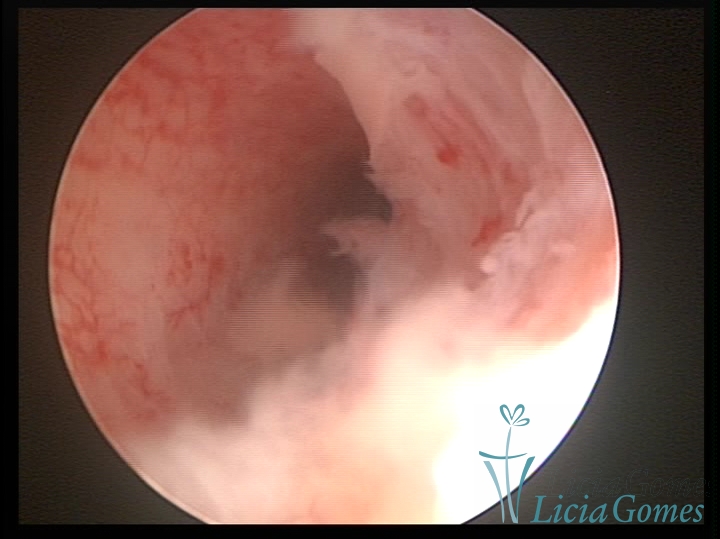

Unicornuate uterus

It presents a tubular cavity with an impaired intracavitary space, resembling the shape of a banana, whose the narrowest edge contains the tubal ostium. The endometrium is compatible with the menstrual cycle and the cervical canal is normal, in structure and trophism.